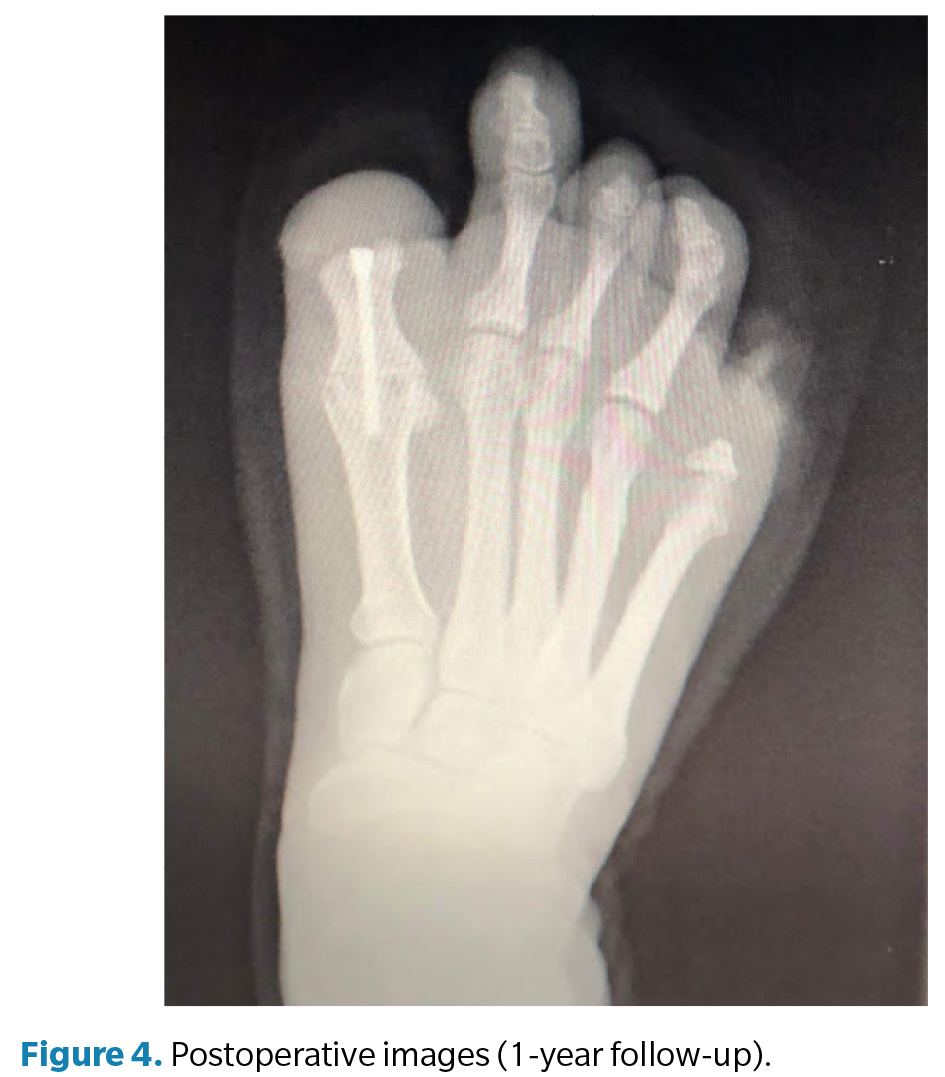

Clinical examination (Figure 2) of the right foot revealed a rigid first metatarsophalangeal joint, with the hallux in fixed plantar flexion and absence of the distal phalanx, producing a painful stump and altered propulsion during gait. The deformity was interpreted as a result of postamputation shortening and cicatricial fibrosis of the residual flexor, with no distal traction. Direct pressure elicited pain over the residual tip of the first toe, which was deformed but retained limited joint mobility. The right fifth toe had a painful hypertrophic scar with a residual corn secondary to total amputation. The left foot showed normotrophic scars at the partial amputation sites of the second and third toes, with no pain or plantar overload, thus requiring no surgery.

Surgery (Figure 3) was performed in March 2022 under regional anesthesia using a posterior popliteal block and conscdious sedation supervised by an anesthesiologist. Antibiotic prophylaxis with 2 g of IV cefazolin was administered 30 minutes before incision, and a pneumatic ankle tourniquet was applied (250 mm Hg), with controlled pressure and ischemia time limited to 45 minutes. A longitudinal dorsal approach to the first metatarsophalangeal joint was performed, preserving neurovascular structures. Irregular bony remnants of the proximal phalanx were identified and completely resected, followed by contouring of bone margins to achieve smooth, viable surfaces. Articular surfaces of the first metatarsophalangeal joint were then prepared by burring and curettage until an adequate bleeding base for arthrodesis was obtained. Fusion position was determined intraoperatively under load testing, fixing the hallux at approximately 10° dorsiflexion relative to weightbearing surface to optimize propulsion and prevent plantar overload on the residual stump. Final fixation was achieved using one cannulated compression screw, ensuring intraoperative stability and correct alignment under fluoroscopy (Figure 4). The procedure concluded uneventfully, with meticulous hemostasis and layered closure.